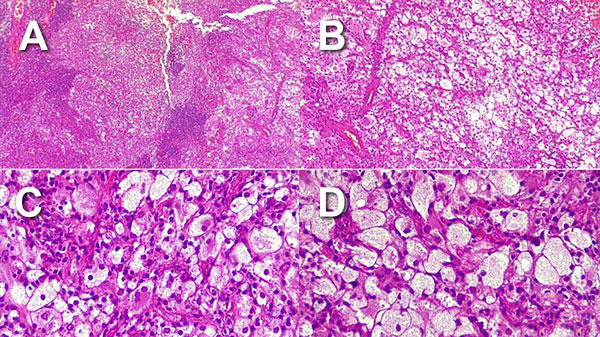

Histopatología: tumor intraaxial temporal compuesto por una población celular heterogénea: células de citoplasmas, amplios claros xantomizados con discreto pleomorfismo nuclear (Figura 3A), alternado con células de menor tamaño con núcleos excéntricos y nucléolos conspicuos (Figura 3B), así como linfocitos y células plasmáticas formando agrupaciones alrededor de la lesión (Figuras 3C y 3D).

Figura 3. Histopatología con coloración de hematoxilina y eosina.

Inmunohistoquímica: reveló positividad para LCA +++/+++ en membrana de linfocitos acompañantes, positividad también para CD138 +++/+++, así como positividad para CD68 +++/+++ confirmando estirpe histiocitaria. En contraste, se demostró negatividad para S100, PGFA, sinaptofisina, citoqueratina, CD1a, IDH-1 y BRAF-V600E (Figura 4).

Figura 4. A) Antígeno leucocitario común (LCA / CD45). Población linfoide positiva. B) CD138 (sindecano-1) positivo. Inmunohistoquímica negativa para C) Proteína S100. D) Proteína gliofibrilar ácida (PGFA) (marcador de diferenciación glial). E) Sinaptofisina, (asociada a la vesícula presináptica). F) IDH-1 (isocitrato deshidrogenasa), no presenta mutación. G) CD1a.